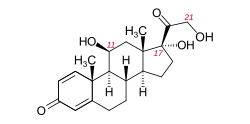

Treatment of Tolosa–Hunt syndrome includes immunosuppressives such as corticosteroids (often prednisolone) or steroid-sparing agents (such as methotrexate or azathioprine).[3]

Although there are known medications for patients, there is not much known about the instructions on administering the medications. Most medications given to patients with this disorder are based on other corticosteroids and other steroids, in which patients will be given a high dosage at first, and as it goes on, the dosage is decreased. Most patients will experience pain relief between 24–72 hours after the medications are given, but these times depend on the type of symptoms that the patient is experiencing.[11] Recurrences are common despite the alleviation of the symptoms. Additionally, depending on the severity of the disorder, not everyone responds the same way. Some patients may respond well to medications, while some patients may not need them at all. Doctors advise on proper diagnosis and evaluation.[12]

Tolosa–Hunt syndrome typically has a good prognosis. Patients usually respond to corticosteroids, and spontaneous remission can occur, although movement of ocular muscles may remain damaged.[3] Roughly 30–40% of patients who are treated for Tolosa–Hunt syndrome experience a relapse.[3]